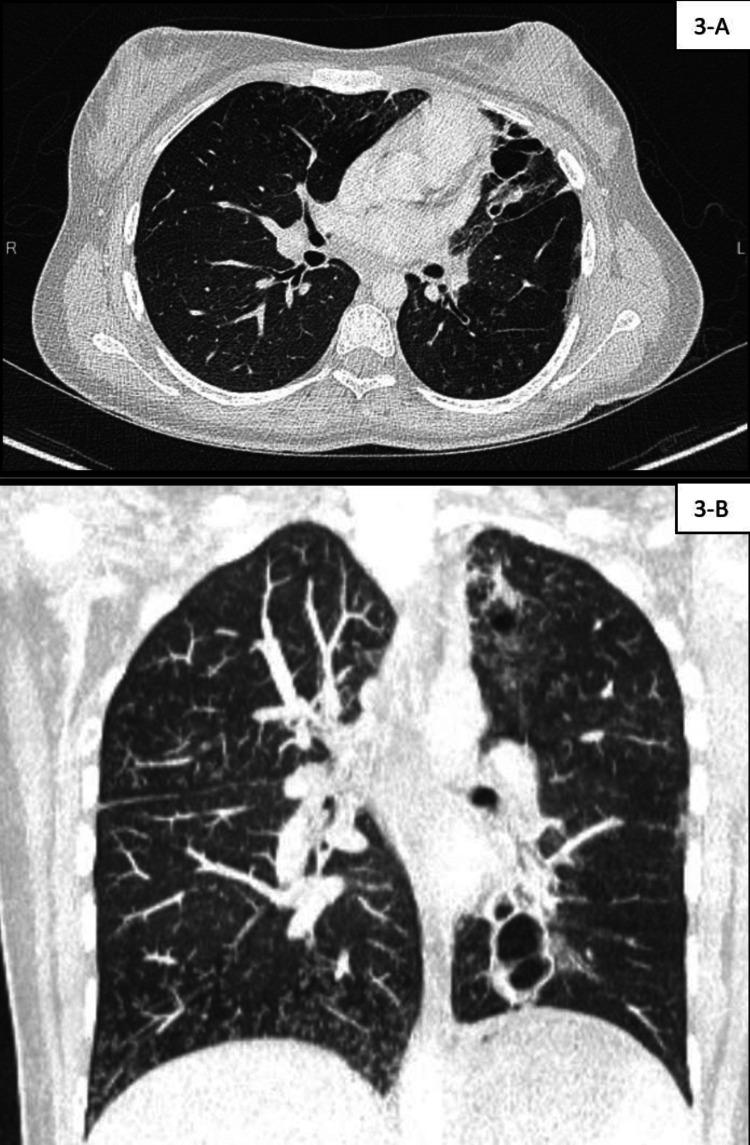

Primary ciliary dyskinesia (PCD) is a heterogeneous autosomal recessive disease marked by organ lateralization in 50% of patients, chronic sinopulmonary disease, infertility in men, and neonatal respiratory distress. Respiratory control cells contain in their apical cytoplasm, which is necessary for the development of multiciliate cells, basal body amplification, and migration. Reduced generation of multiple motile cilia, a rare form of PCD, has been linked to gene abnormalities Individuals with mutations have been reported to suffer from severe lower respiratory infections that cause progressive impairment of lung function. For the first time, we describe the (c.258 262dup.p, Gln88argfs*8 Homozygous) gene mutation in an Indian consanguineous family that resulted in severe PCD.

原发性纤毛运动障碍(PCD)是一种常染色体隐性遗传病,具有异质性,其特征为50%的患者出现器官定位异常、慢性鼻窦肺部疾病、男性不育以及新生儿呼吸窘迫。呼吸控制细胞在其顶端细胞质中含有(某种物质),这对于多纤毛细胞的发育、基体扩增和迁移是必需的。多根活动纤毛生成减少是PCD的一种罕见形式,它与(某个)基因异常有关。据报道,携带(该)基因突变的个体患有严重的下呼吸道感染,可导致肺功能进行性损害。我们首次在一个印度近亲家庭中描述了(某个基因)(c.258 262dup.p,Gln88argfs*8纯合子)基因突变,该突变导致了严重的PCD。